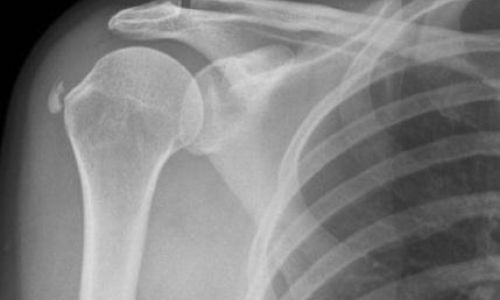

Η ασβεστοποιός τενοντίτιδα του ώμου αποτελεί μια συχνή πάθηση των ενηλίκων. Η πάθηση χαρακτηρίζεται από την εμφάνιση ασβεστώματος με συνοδό φθορά στους τένοντες των μυών του στροφικού πετάλου του ώμου (υπερακάνθιος και υπακάνθιος). Η πάθηση είναι κυρίως ιδιοπαθής. Εμφανίζεται συχνότερα σε γυναίκες και κυρίως σε άτομα της ηλικιακής ομάδας από 30-60 ετών. Στατιστικά συνδέεται με την ύπαρξη 2 συνοδών νοσημάτων, του σακχαρώδη διαβήτη (Σ.Δ.) και του υποθυρεοειδισμού. Η κλινική εικόνα είναι η εξής. Ο ασθενής εμφανίζει έντονο άλγος στην περιοχή του ώμου με συνοδό μείωση του εύρους κίνησης της άρθρωσης. Το άλγος μπορεί να είναι και νυχτερινό ενώ η αδυναμία της κίνησης μπορεί να οδηγήσει στη δημιουργία συμφύσεων στον ώμο και εμφάνισης του συνδρόμου παγωμένου ώμου (frozen shoulder).

Η διάγνωση επιβεβαιώνεται συνήθως με μια απλή ακτινογραφία ενώ σε περιπτώσεις που χρειάζεται αρθοσκοπική αποκατάσταση γίνεται και μαγνητική τομογραφία ώμου.